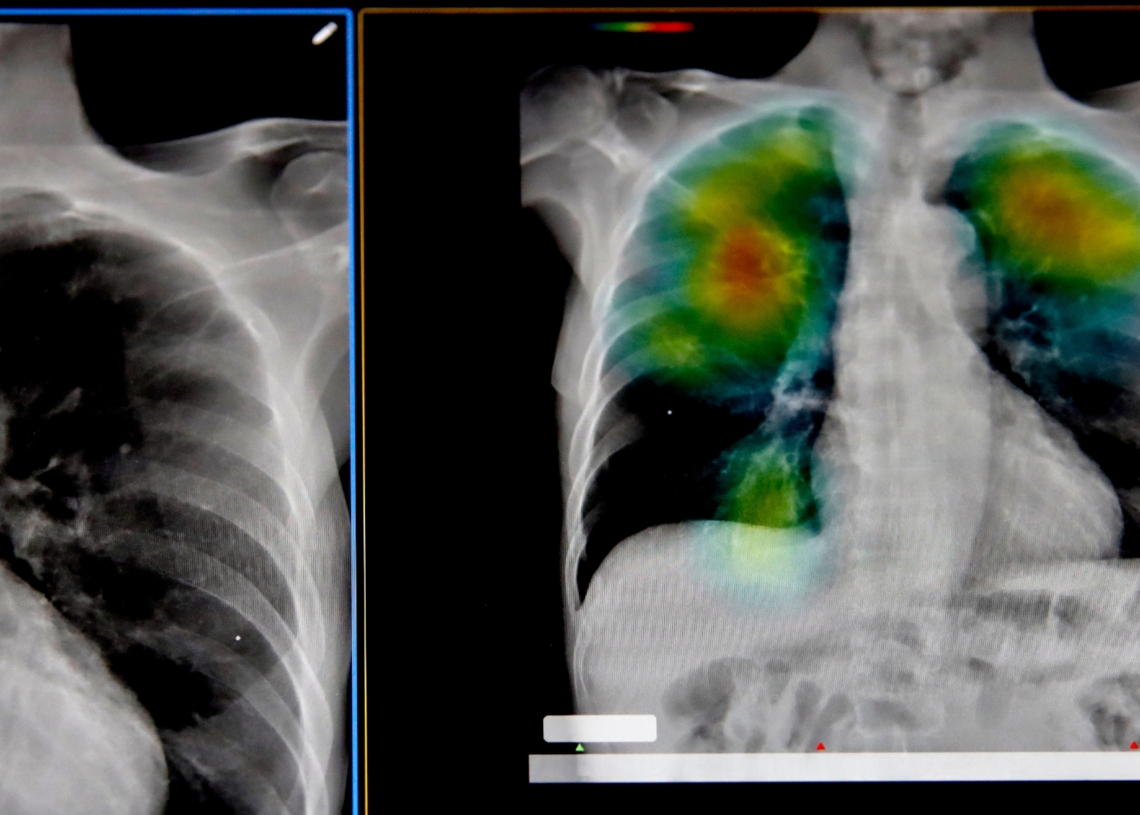

As some sectors of the AI industry seem dead set on replacing the hard, creative work put in by actual humans deserving of jobs, others are putting the technology to a more societally enriching use: using AI to predict diseases before symptoms even start.

The approach, presented as an editorial in the journal Intelligent Medicine by a team of researchers from China, is not just a technological shift but a fundamental rethinking of how doctors diagnose patients. Diagnosing a disease today can take several visits to different doctors and numerous tests, with a lot of time in between as a patient waits for results. The researchers want to use AI to monitor how networks of genes, proteins, and chemical signals change over time, looking for instability in the body that signals something is about to go wrong. The keyword here is about.

It’s an approach aligned with something called the dynamic network biomarker theory. It suggests that as the body approaches disease, certain molecular networks begin to fluctuate and become more interconnected than usual. In studies of influenza, for instance, these patterns begin to emerge in the days before symptoms appear. In cancer research, they identified similar signals emerging around the point where cells start to turn malignant. The prediction accuracy of these patterns is somewhere above 80 percent.

This AI Could Help Predict Disease Before Symptoms Appear

One drawback of modern diagnosis is that it relies on population averages to determine when symptoms may arise. Newer AI methods would shift the focus to the patterns specific to a single person. It’s mostly theoretical right now, but in practice, it would mean we could use AI to tailor health monitoring to each person.

These tools will be especially handy for tracking the body’s small molecular networks as they change in response to, say, type I diabetes, where these AI models can’t predict blood sugar levels a lot more accurately than older predictive tools by creating digital simulations of an individual. This same idea can be applied to a variety of health issues, including heart failure.

There are still plenty of hurdles to overcome before we reach the point of AI predicting a tumor long before symptoms crop up. The system is heavily dependent on a constant stream of clean data. Without it, or even just with big gaps, the system can trigger all sorts of false alarms, detecting correlations that don’t actually have real causation. And there’s also the pesky matter of AI hallucinations, which in the medical world is known as a black box, which is when an AI model spits out a prediction that even its own designers can’t explain.

None of this is to say that AI will replace doctors anytime soon, or even ever. At best, it’ll just be an early warning system that flags risks before symptoms appear. It would still be up to a medical professional specializing in that field to interpret the results and determine whether the AI was correct or making connections where none existed.